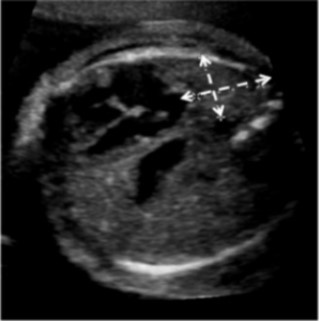

Charts were retrospectively reviewed for observed-to-expected (O/E) values for U/S LHR, MRI FLV measurements, and outcome of the pregnancy and fetus. O/E values normalize measurements to the gestational age of the fetus. MRIs were also retrospectively reviewed by a single pediatric radiologist for location of the stomach. Stomach location was simply defined as all, some, or none of the stomach in the thorax (Figure 2). The primary outcome was survival to discharge. Ultrasound O/E LHR and MRI O/E FLV was compared for all fetuses. An U/S LHR < 1, U/S O/E LHR < 15%, and MRI O/E FLV <25% were considered predictors of poor outcome, and these values were utilized to determine if the various measurements correlated.

Figure 2.MRI demonstrating the entire fetal stomach (black arrow) in the thoracic cavity. The white arrow points to the fetal diaphragm.

MRI demonstrating the entire fetal stomach (black arrow) in the thoracic cavity. The white arrow points to the fetal diaphragm.

Since none of these typical prognosticators are ideal and other measurements such as the McGoon index are also complex to obtain, we investigated simply using stomach position on MRI as a prognostic indicator. The location of the stomach serves as a marker of defect size, visceral herniation, and pulmonary hypoplasia. Here we report that those patients with some or no stomach in the thorax have significantly higher U/S LHR, U/S O/E LHR, and MRI O/E FLV than those with all of their stomach in the chest. Furthermore, all patients who had just some or no stomach in the chest on MRI survived to surgery and discharge. Therefore, lack of the entire stomach in the thorax on MRI is a good prognostic indicator.